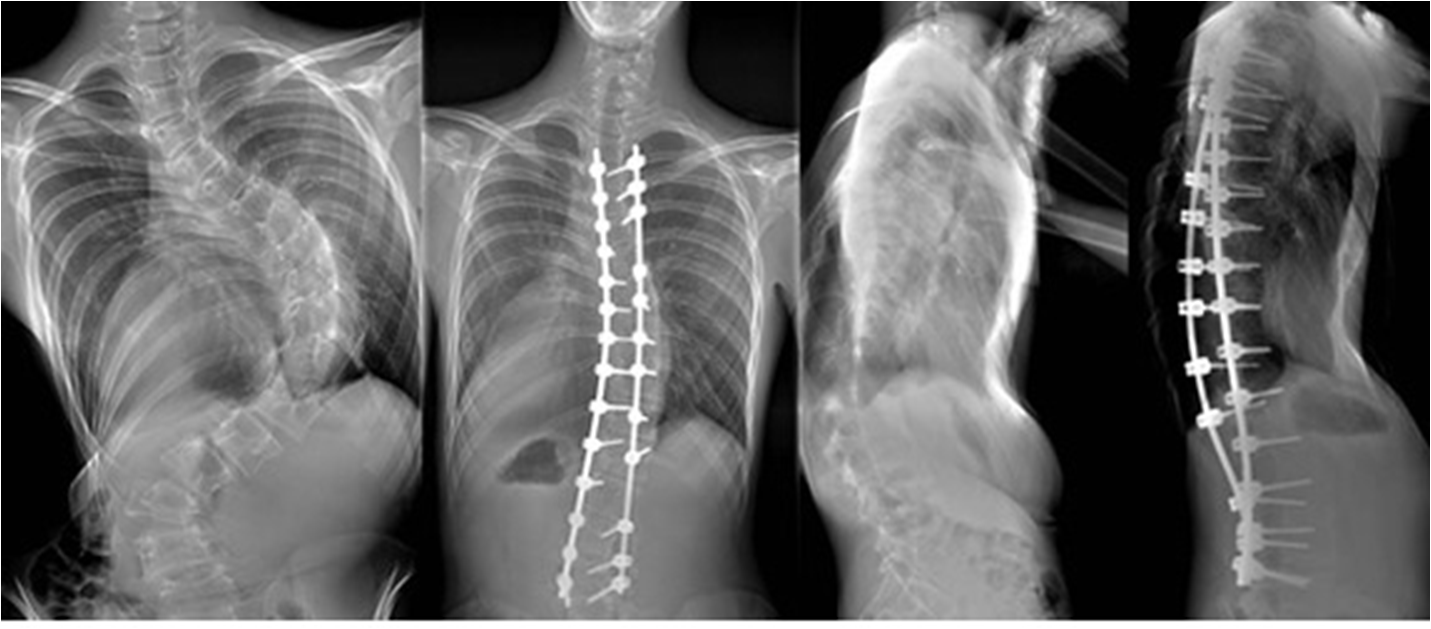

Cobb's각이 40도 이상일때 시도하며 키의 성장이 남아있고 측만증이 급속히 악활 될 때 교정력 60~70%를 목표로 수술을 시행 한다. 수술후 수술부위는 성장이 멈추고 구부리고 펴는 기능을 상실하게 된다.